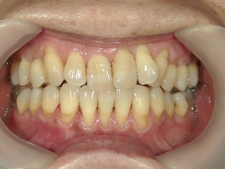

矯正歯科 治療前矯正歯科 治療前

64歳女性 浜松市中区在住

治療期間 7カ月

矯正歯科 治療前